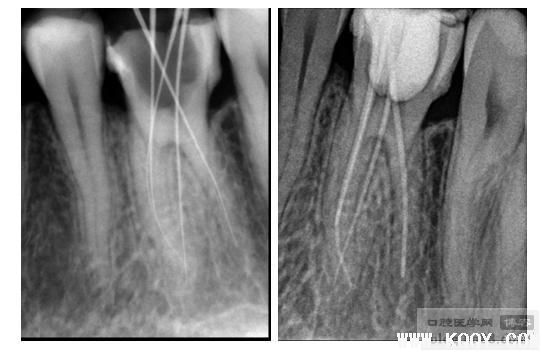

处:16RCT后行桩核冠修复。局部麻醉下行开随,DG探针探根管口(发现MB2),去髓,电测根长,机扩NI-TI备根,MB19mm 30#,MB2 21mm 30#,DB20mm 30#,P19.5mm 35#,根充糊剂,热牙胶充填,暂封。

插针片(MB与MB2属于2-1分型) 试尖片(NI-TI预备后)